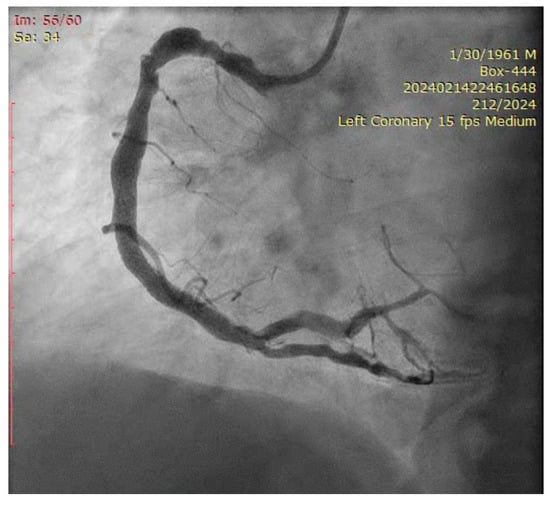

- Performing the first Trissing with 1:1 NC balloons sized to the distal branches’ diameter (3.5, 3.5, 4.0 mm) (Figure 15).